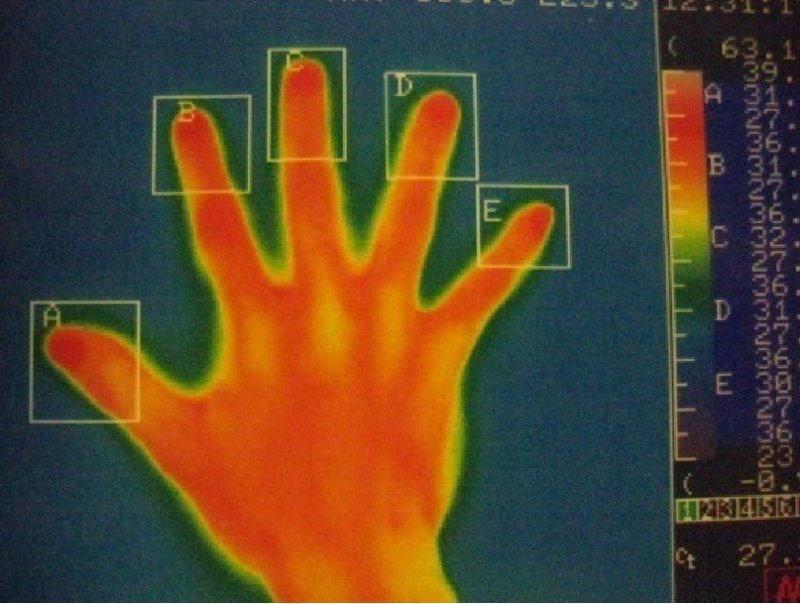

サーモグラフィー

左手

右手

赤い部分が高温部位を示しています。

左手

右手

明らかに両手の体温の低下がみられ、術直後から多汗症の症状は消失します。